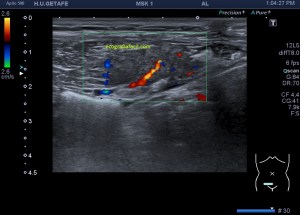

Una de ellas, la primera, era mucho más hiperecogénica y más pequeña, su centro estaba mas calcificado, su sombra acústica posterior era mucho más acuciada y llamaba más la atención. Justo al lado, otra lesión de mayor tamaño, su calcificación era mucho más sutil y más periférica delimitando una LOE hipoecogénica de un tamaño muy importante, adyacente a la más pequeña, como he comentado previamente. Ambas sin señal Doppler.

La LOE es de aspecto redondeado, heterogéneo, con multitud de pequeñas imágenes anecoicas e hipoecogénicas, de diferentes tamaños. Esta lesión fue estudiada también mediante otra técnica de imagen, la RMN donde se observa una imagen hiperdensa, con una amalgama de lesiones bordeando a periferia de la misma, de distintos tamaños como se objetiva en la imagen del mismo paciente, de la ecografía inmediatamente superior (Imagen 7). La lesión es activa, por tanto debió de ser tratada, la patología es potencialmente mortal en caso de que el quiste se rompiese.